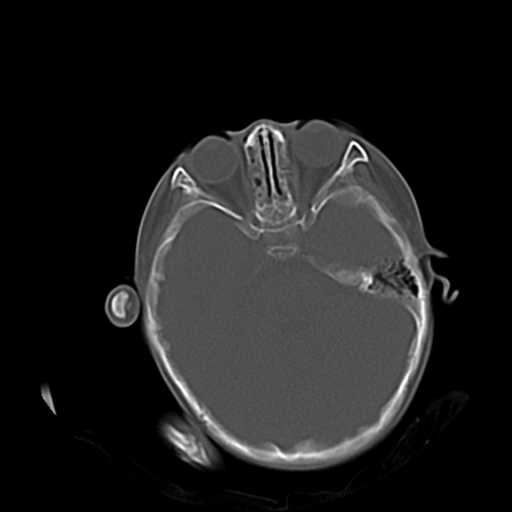

m,3y,外伤一天,无明显其它症状.

1.双侧上颌窦、筛窦炎。

2.左侧上颌窦后壁部分骨质缺损,内有一牙齿样高密度,周围似乎无明显囊肿形成(没有继续往下扫描,而且只有骨窗,不便观察)。暂考虑左侧上颌窦牙源性囊肿可能。

3.小脑以及右侧颞叶无明显异常,颅盖以及颅底诸骨未见明显骨折,双侧枕骨内板蛛网膜粒压迹多、略深。